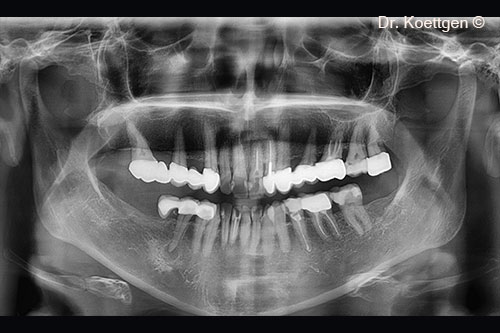

Một bệnh nhân nữ (45 tuổi) có biểu hiện teo xương hàm dưới.